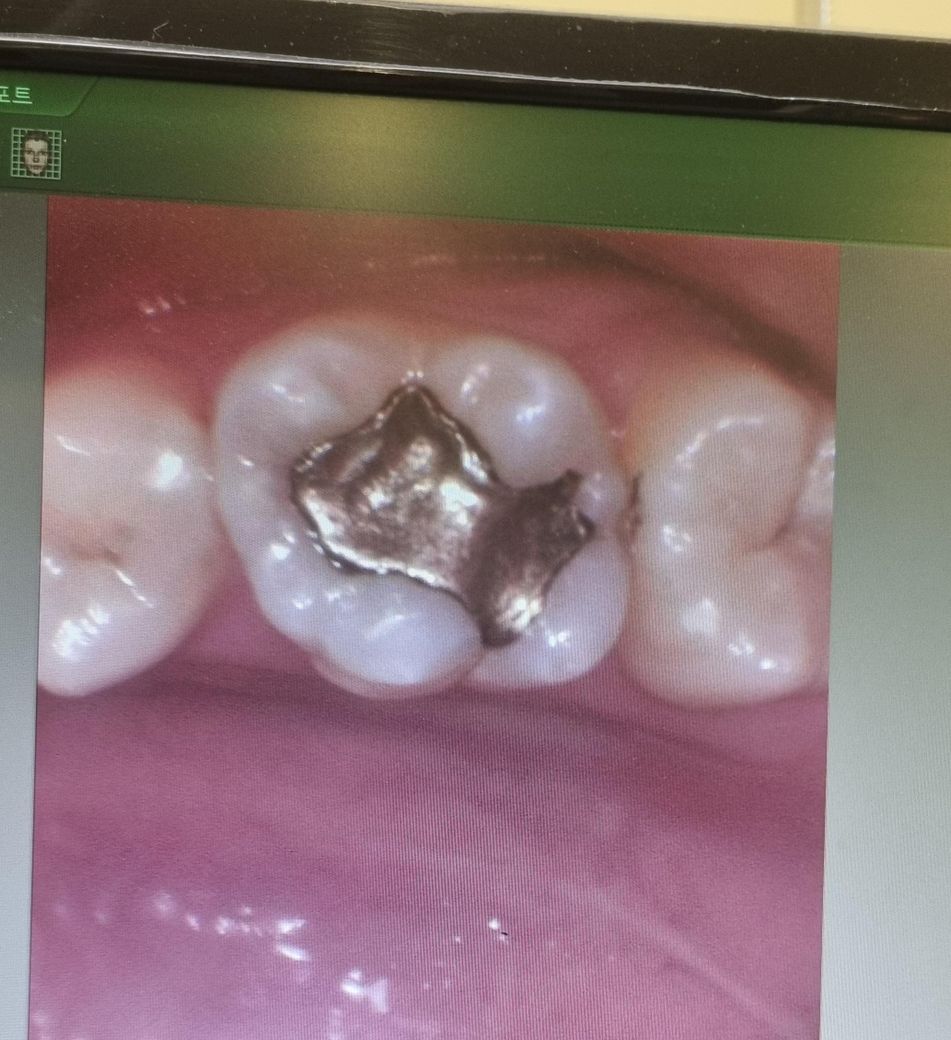

이거 충치를 꼭 치료해야할까요???

충치가 있다고 레진으로 떼워야한다고 하는데 꺽 치료해야할 정도일까요??

통증은 없어서 고민이되네요....

오히려 작은 충치를 치료하면 나중에 문제가 생긴다고 들어서 ㅠㅠ

• 1번 째 사진

사진상으로 충치가 잇어 보입니다 엑스레이 촬영을하고나서 상태확인후 치료가 필요 할것같습니다.

1. 올려주신 사진중 첫번째는 보기보다 충치가 안쪽으로 좀 깊게 있을 수도 있습니다